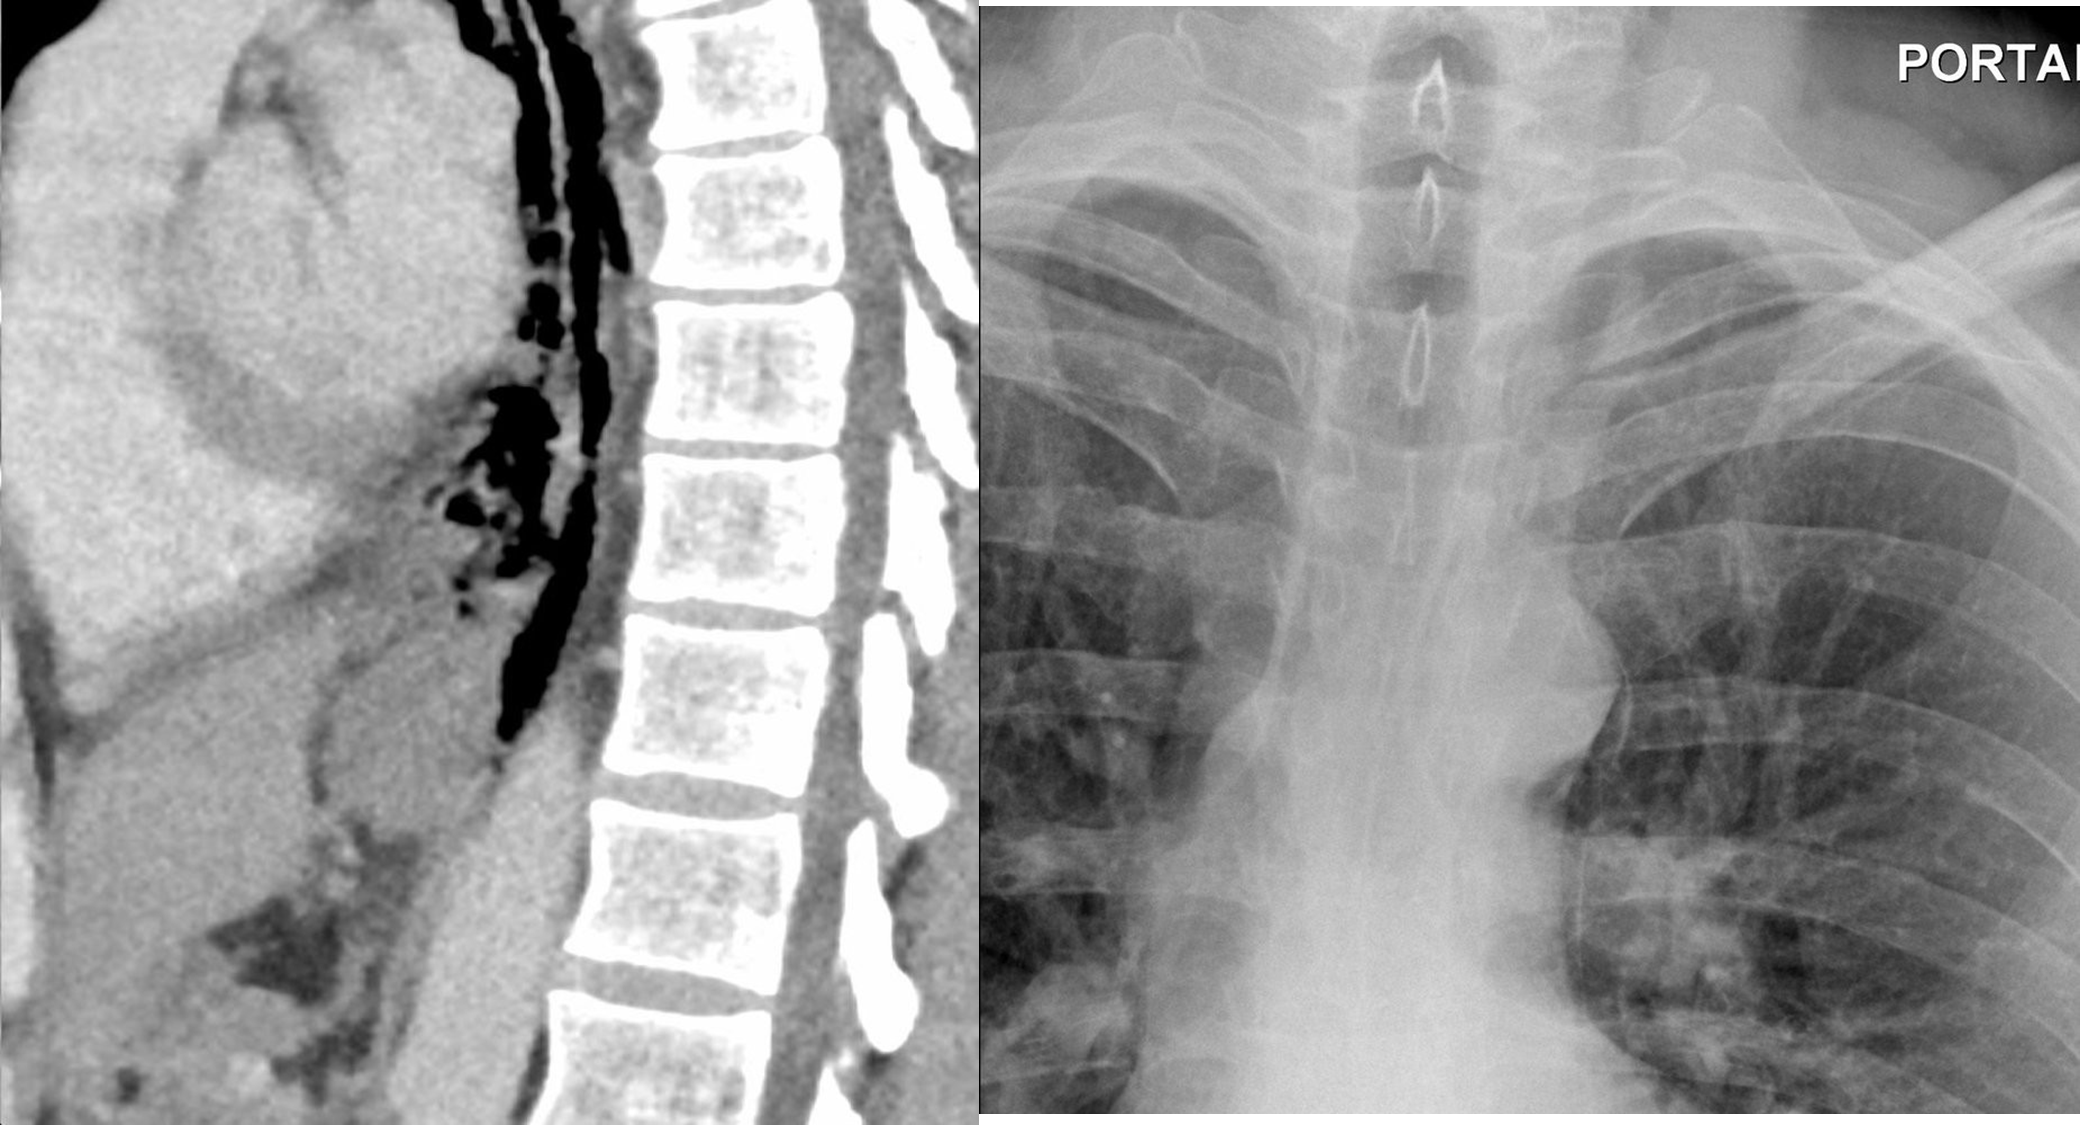

What is your diagnosis Dissecting aortic Aneurysm

Mediastinal air (pneumomediastinum) Oesophageal rupture

Left Sided Massive Pleural Effusion with Mediastinal Shift